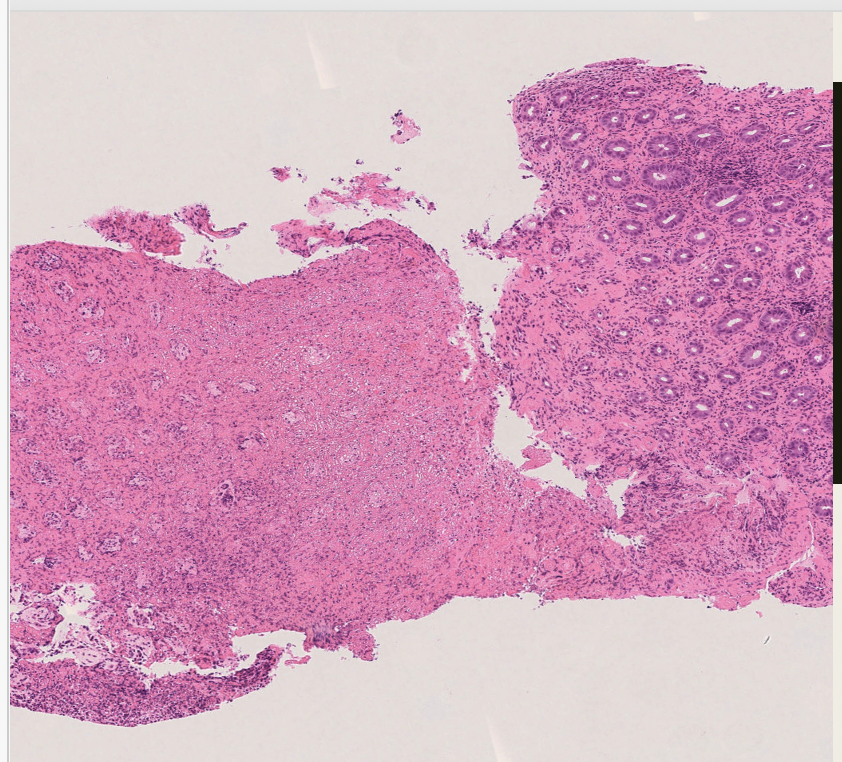

Crohns disease- macro and micro features

Macro:

Micro:

Ulcerative colitis - macro and micro